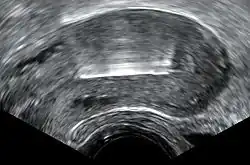

Expulsion rates can range from 2.2% to 11.4% of users from the first year to the 10th year. The TCu 380A may have lower rates of expulsion than other models, and the frameless copper IUD has a similar rate of expulsion to models with frames.[22][23] Expulsion is more likely with immediate or early postpartum or post-abortal placement.[24][25] In the postpartum period, expulsion is less likely when the device is placed less than ten minutes after the placenta is delivered, or when inserted after a cesarean delivery.[16] Unusual vaginal discharge, cramping or pain, spotting between periods, postcoital (after sex) spotting, pain during intercourse (dyspareunia), or the absence or lengthening of the strings can be signs of a possible expulsion.[21] As with intentional removal, the device is immediately ineffective after expulsion. If an IUD with copper is inserted after an expulsion has occurred, the risk of re-expulsion has been estimated in one study to be approximately one third of cases after one year.[26] Magnetic resonance imaging (MRI) may cause dislocation of a copper IUD, and it is therefore recommended to check the location of the IUD both before and after MRI.[27]

Perforation of the device through the uterine wall typically occurs at the time of placement, though it may occur spontaneously during the period of use. Estimates of the rate of perforation vary from 1.1 per 1000 to 1 per 3000 copper IUD insertions.[1][11] Perforation may be slightly more common in people using the copper IUD while breastfeeding.[28]

Due to its inflammatory mechanism of action, a copper IUD that has completely perforated typically requires surgical removal due to the formation of dense adhesions around the device. A device embedded in the uterine wall may be removed hysteroscopically or surgically.[1][16]